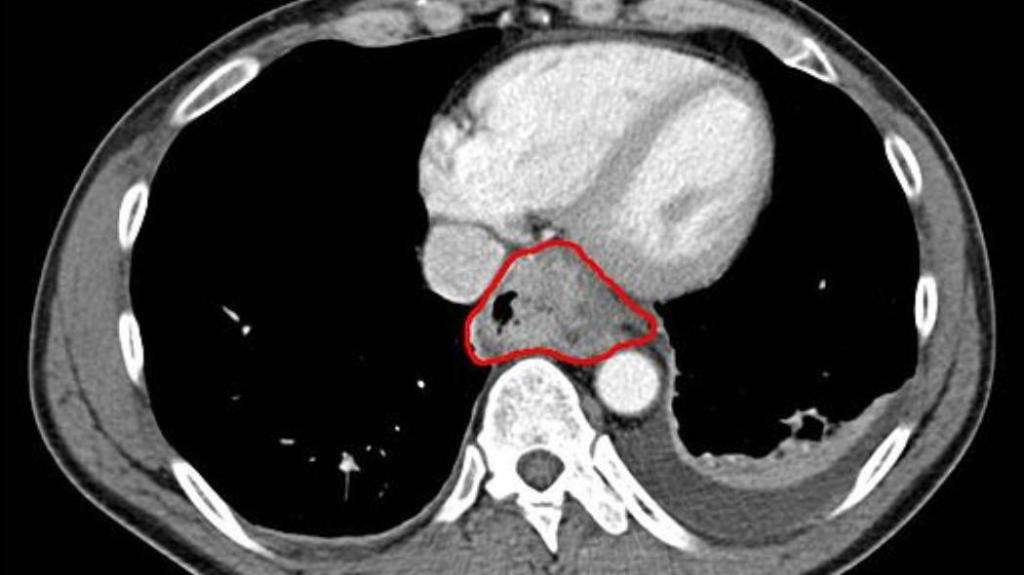

Programul, intitulat CancerLocator, detectează ADN-ul tumorilor în mostrele de sânge ale pacienților și indică exact unde anume se situează tumoarea în corp. În cadrul unui mic studiu pilot, a diagnosticat cu succes cancerul de ficat, plămâni și sân în optzeci de procente dintre cazuri, ceea ce le-a dat cercetătorilor speranța că programul ar putea fi folosit la consultațiile obișnuite, fără să mai fie nevoie de biopsii invazive.

Dezvoltat de cercetătorii de la Universitatea California, Los Angeles, și Universitatea din California de Sud, CancerLocator funcționează prin analizarea ADN-ului care ajunge în fluxul de sânge după ce mor celulele. Fiecare fragment de ADN are un tipat unic de substanțe chimice, numite grupuri metil, care marchează care gene sunt active sau inactive. Acești markeri de metil pot indica dacă o genă a fost întreruptă la o celulă canceroasă. Și, din cauză că celulele și țesuturile diferite au gene diferite care sunt activate în corp, tiparele de metilare pot funcționa și ca amprentă a originii ADN-ului.

Zhou și colegii ei au adăugat puterea de învățare aparatelor la un test de sânge. Au folosit informații disponibile în baza de date disponibile în Atlasul Genomului Cancerului ca să învețe software-ul CancerLocator să recunoască tiparele normale și tiparele care indică tumori. Asta le-a permis cercetătorilor să detecteze cancerul chiar și în situațiile în care cantitatea de ADN secvențiat era foarte mică.

În cadrul unor teste de sânge pe 29 de pacienți cu cancer la ficat, 12 pacienți cu cancer la plămâni și cinci paciente cu cancer la sân, programul a reușit să reducă erorile în detectarea cancerului de la șaizeci de procente la 26,5 procente.